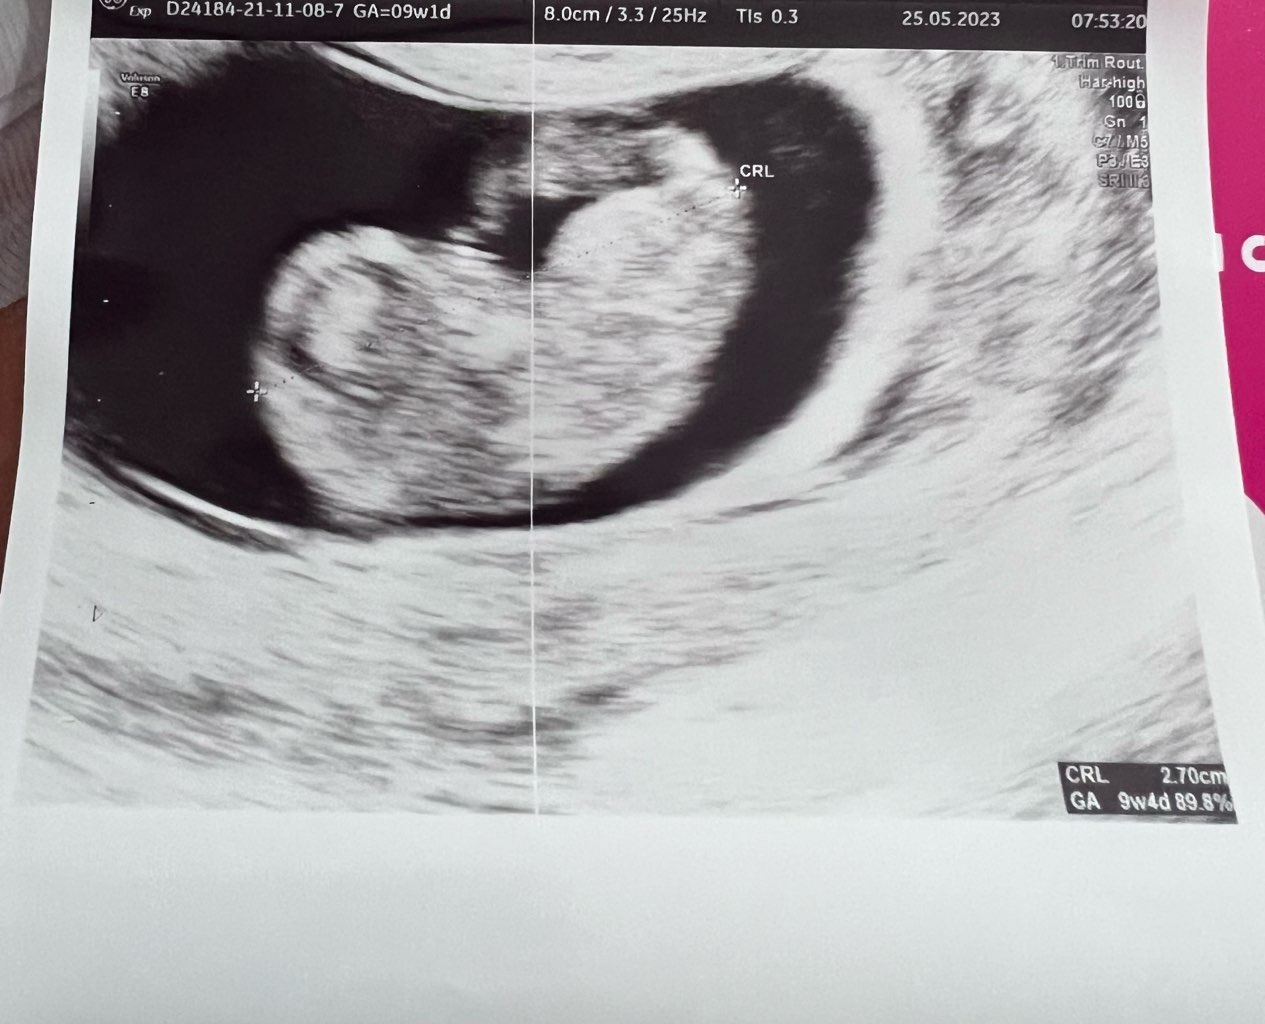

Dzień doberek! Jak tam się czujecie? Ja po wizycie i wyglądamy teraz tak. Prenatalne umówione na 14.06